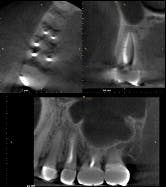

The report from the ENT was negative. The symptoms persisted and, in fact, started to worsen. The likelihood of a vertical root fracture was then discussed with the patient. He was referred to an endodontist who took a CBCT scan.

Evaluation by the endodontist showed a very small direct, vertical 9 mm drop on the lingual with radiolucency on the lingual root in the scan about halfway down (figure 12). Given the history of the double root canal, symptoms, and radiographic evidence, it was concluded that the patient had sustained a vertical root fracture on the lingual root of tooth No. 4. Prognosis was poor, and the tooth was removed with discussion regarding replacement options.

Editor’s note: The CBCT scan in case No. 2 (figure 12) is courtesy of Joseph A. Petrino, DDS, MS; Missoula, Montana.